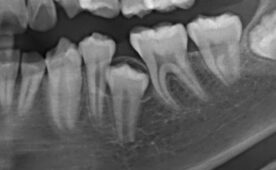

60代女性。3年前に他院にて自費治療で入れたセラミックの詰め物が…